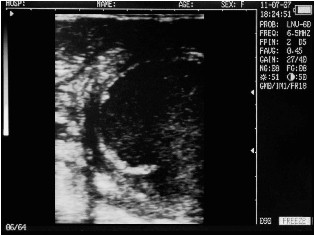

Filled bladder cow